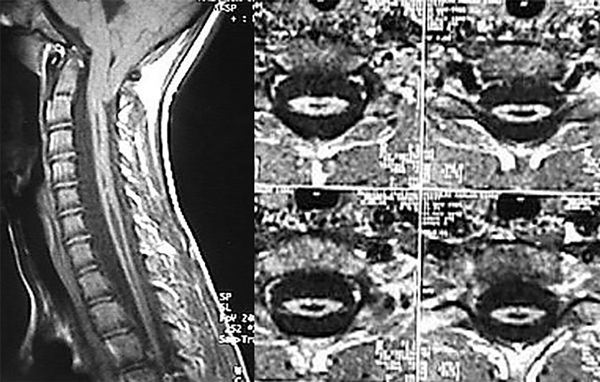

A la edad de 10 años y 6 meses, el niño presentó hiperestesia cutánea abdominal izquierda e hipotrofia de cintura escapular, asociados a signo de Babinsky bilateral. Se recomendó realizar cirugía de la malformación de Chiari, pero la familia rechazó dicha propuesta de tratamiento. Un año después, sorpresivamente, el control con RM mostró una marcada reducción del tamaño y diámetro de la siringomielia cervicotorácica, cuyo aspecto era fusiforme (Figura 2).

Figura 2. Cortes sagital y axiales de RM en los que se evidencia el colapso de la cavidad.